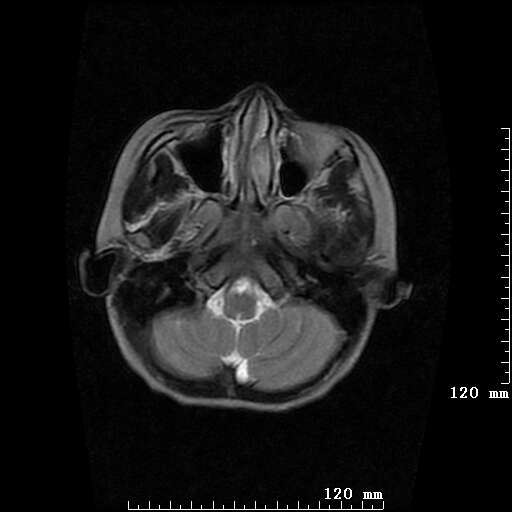

女,7岁,三岁才说话、走路。现智力尚可,走路不稳。临床怀疑大脑发育不全。

考虑 脑白质发育不良

脑折质变薄,双侧侧脑室稍扩张,支持考虑脑折质发育不良

考虑胼胝体发育不全,髓鞘形成不良。

支持考虑胼胝体发育不全,髓鞘形成不良。

脑裂畸形伴灰质异位

侧脑室周围白质数量减少,侧脑室不对称性扩大,左侧侧脑室后角呈方形改变,脑沟加深,结合临床考虑脑室周围白质软化症(pvl)。期待结果!